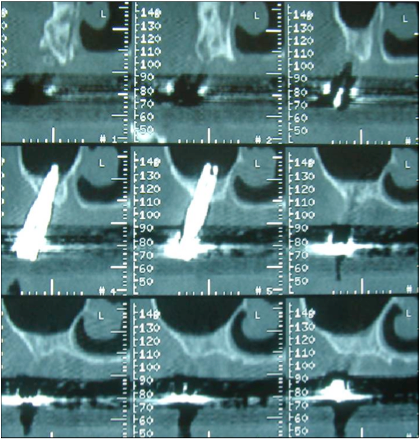

photo d’implant dans le sinus

Il en résulterait une infection sinusienne avec perte des implants et risque de communication bucco-sinusienne (trou entre le bouche et les sinus).